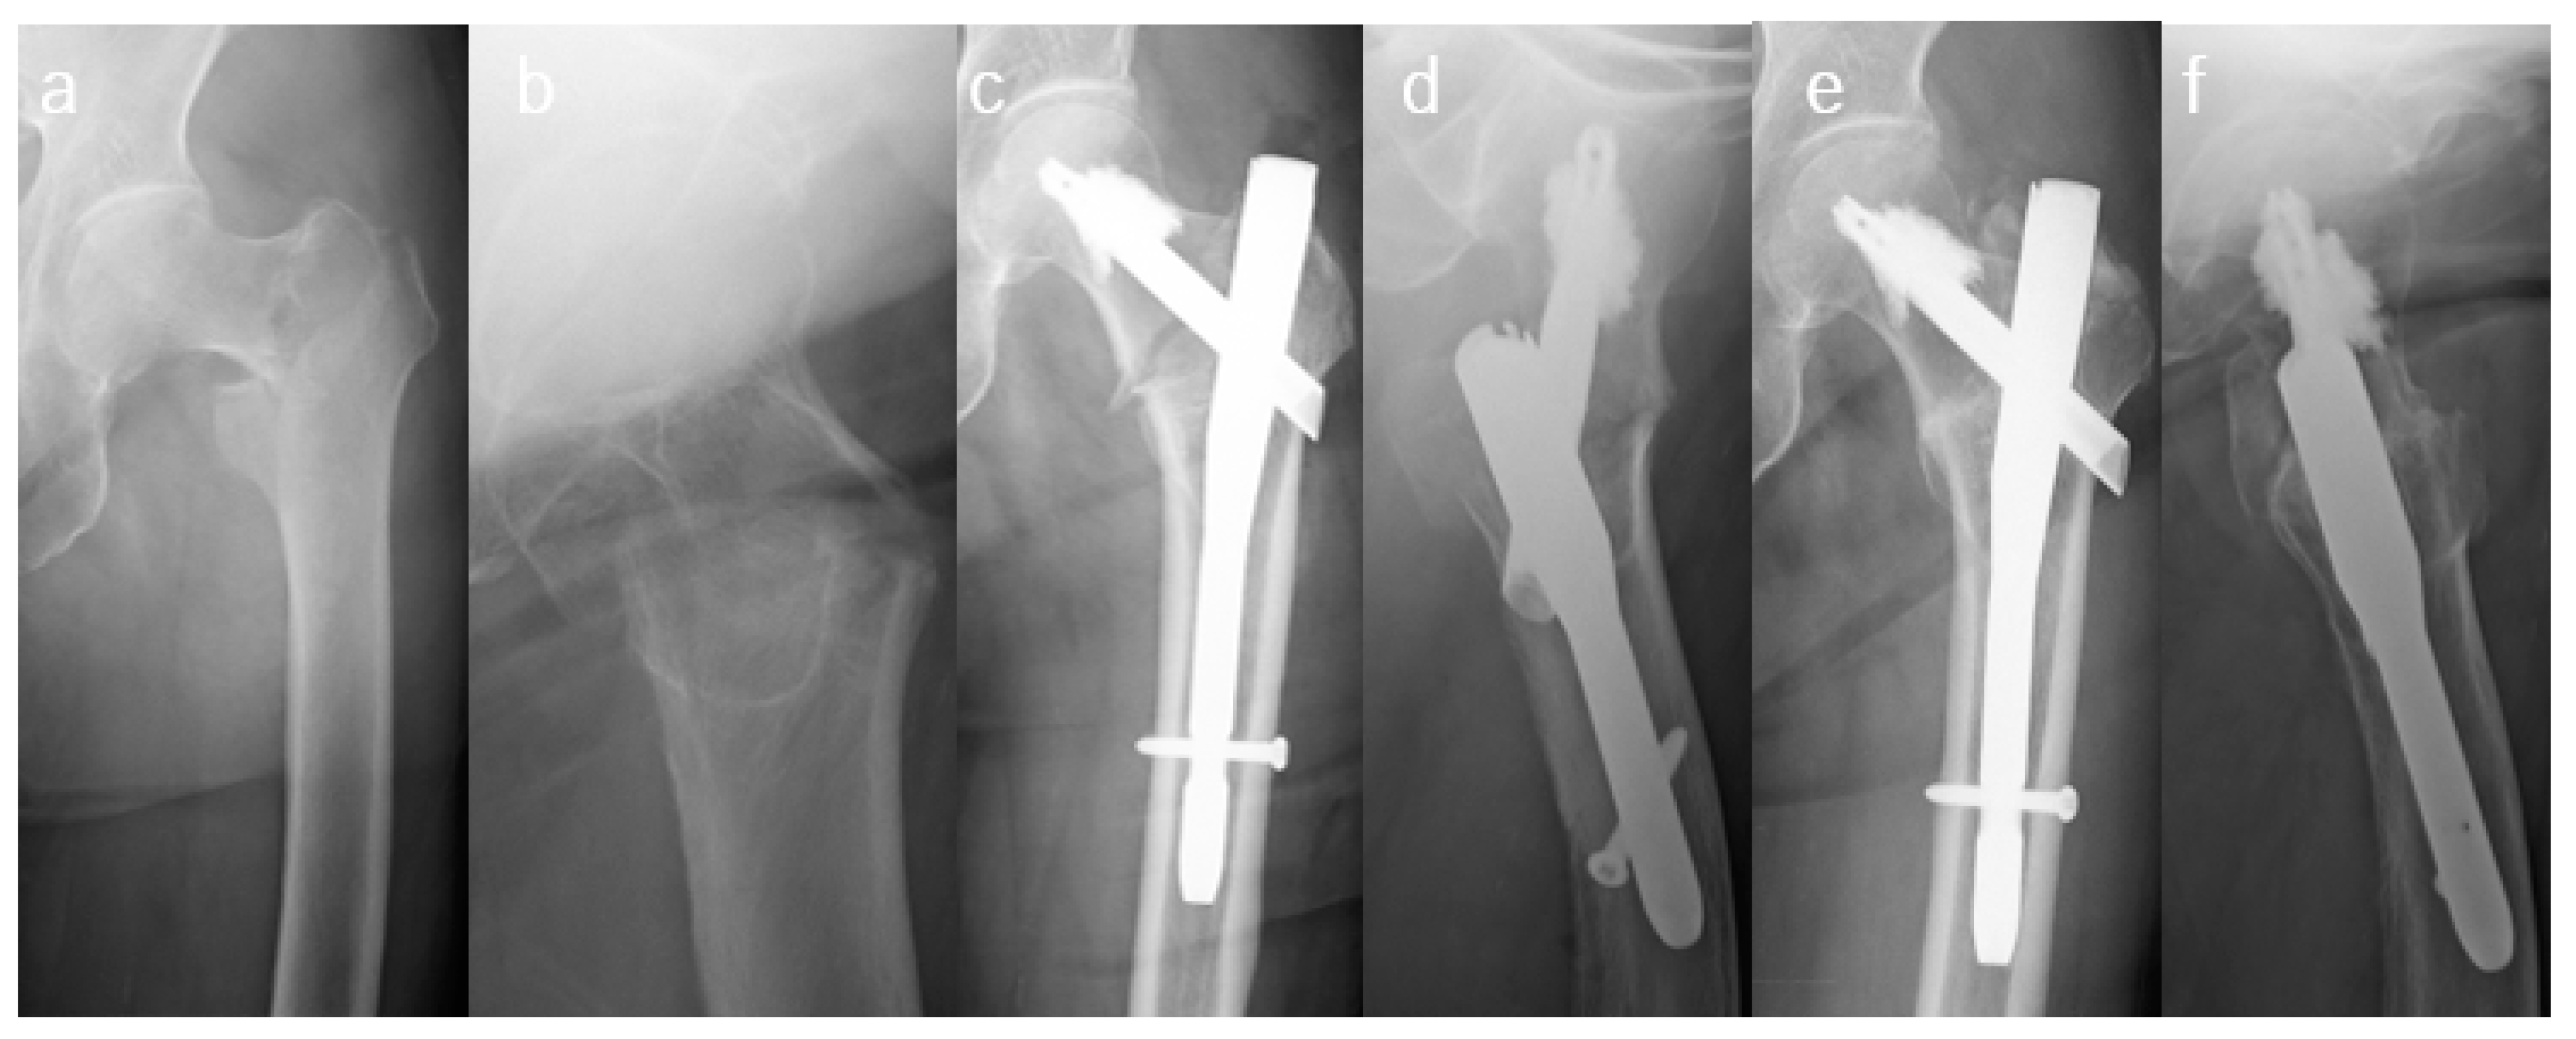

2.3. Surgical Procedures and Rehabilitation Plan

2.4. Main Exposure